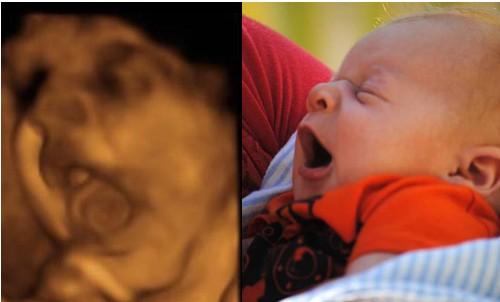

真的是这样吗?专家解答说,其实四维彩照出来的成像与宝宝出生后的模样会有一定出入,以下三张图片告诉你。

2、 四维照片是一个大致影像

如果朋友们去做过B超应该知道,医生会在仪器上涂满凝胶,然后再放到患者肚皮上来回滑动。为取到完整的图像,所以得多角度去探索。

但是小宝宝的口耳鼻实在太细节,声波反弹较弱,因此连接到电脑上后会另外填充成像。毕竟四维彩照和我们平时拍照的像素不一样,它是由彩超探头采集到的数据以此合成一个大致的影像。

那么打印出来后自然模糊,边缘不清晰,导致小宝宝的五官和肢体看起来扭曲变形。一定程度上*化丑**了宝宝,让新手爸妈们怀疑人生。

综上所述,四维彩照出来的胎儿成像,并不会是宝宝实际出生的样子。就和我们去一个餐厅吃饭一样,实物与图片不符。

不过,刚出生的宝宝大概率上不会好看,毕竟在羊水里面泡了太久,皮肤都皱巴巴的了。当宝宝过一个礼拜后会变得逐渐白皙,一个月后五官慢慢长开,那个时候就相当可爱啦。